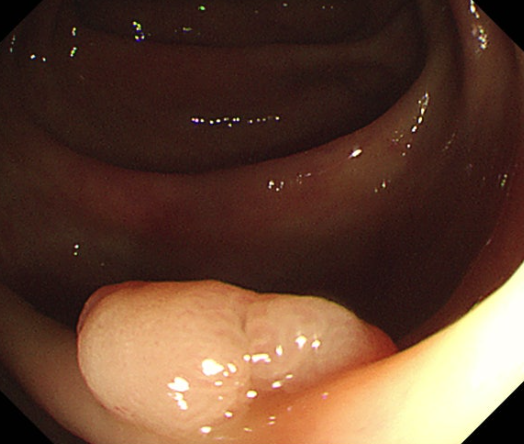

장 점막이 비정상적으로 자라 혹이 되어 장의 안쪽으로 돌출되어 있는 상태로 대장의 양성 종양 중 선종성 용종이 2/3~3/4 정도를 차지하고 있으며 대장의 양성 종양을 대장 용종이라고 합니다.

용종이 많은 경우를 다발성 용종이라고 하며, 100개가 넘는 경우는 용종증이라고 합니다.

대부분의 대장용종은 양성이지만, 일부는 시간이 지나면서 암으로 발전할 수 있으며 선종성 용종은 대장암의 전구 병변으로 알려져 있어 주의가 필요합니다.

1) 대장내시경적 용종절제술 (Polypectomy)

대장내시경을 통해 용종을 발견하면, 내시경에 부착된 작은 루프를 사용하여 용종을 잘라내거나 태워 제거합니다.

이는 가장 흔한 치료 방법이며, 시술 후 용종은 암 여부를 판단하기 위해 조직 검사를 받게 됩니다.